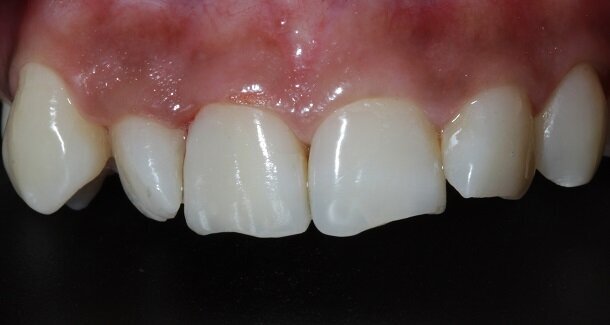

Presenting a case of a 22 yr old male, who reported to our dental office with fractured Maxillary Central incisors many years ago [Figures 1 and 2]. On examination both Maxillary Central incisors had fractures with pulp exposures. IOPAR showed large peri-apical lesions in both teeth. There was no mobility seen in either teeth, but discolouration was seen in both. Non-surgical Endodontic treatment followed by Bleaching and Direct composite restorations (2 weeks post bleaching) were planned.

The figures show the clinical work flow involved. In the 1st appointment Oral prophylaxis, oral hygiene instructions were followed by an impression that was sent to the lab for a wax up [Fig 3 and 4]. In the subsequent appointments, Endodontic treatment was followed by Intra and extra coronal office bleaching using the Pola office bleaching kit. After two weeks, the shade stabilised post bleaching. Shade selection, rubber dam isolation and preparation was done on both the teeth to receive Direct composite veneers so as to close the midline diastema as well as correct the fractured teeth and the slight mal-alignment. Controlled Body Thickness (CBT) technique of layering was used with 3M Z350XT shades - Dentin shades A3, A2 and Enamel shades A2, clear translucent [Figures 5 to 11]. This was followed by the Finishing and polishing protocol as described in the figures.